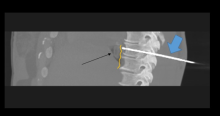

J. David Prologo, MD, FSIR, ABOM-D. Co-Investigators – Emory Interventional Radiology